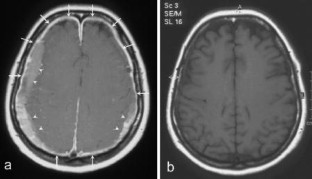

Abb. 1a,b